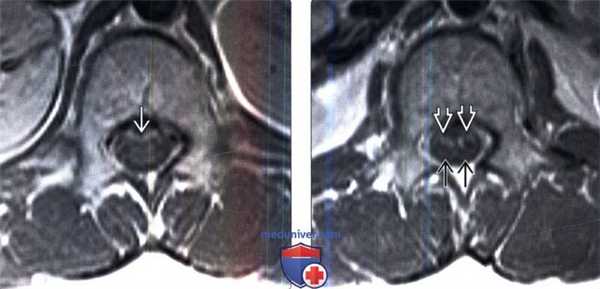

(Слева) Сагиттальный срез, Т1-ВИ, пациент с лейкозом и парезом нижних конечностей после интратекальной химиотерапии, изменения со стороны конуса спинного мозга и корешков конского хвоста не видно.

(Справа) На сагиттальном Т1-ВИ с КУ у этого же пациента отмечается патологическое равномерное линейное контрастное усиление мягкой мозговой оболочки конуса спинного мозга и корешков конского хвоста.

(Слева) Аксиальный срез, Т1-ВИ с КУ: на уровне конуса спинною мозга отмечается равномерное тонкое линейное контрастное усиление мягкой мозговой оболочки вентральной поверхности конуса спинною мозга и конского хвоста.

(Справа) На аксиальном Т1-ВИ с КУ на уровне конского хвоста определяются характерные признаки равномерного тонкою линейного контрастного усиления вентральных корешков конскою хвоста, дорзальные корешки при этом выглядят нормально.